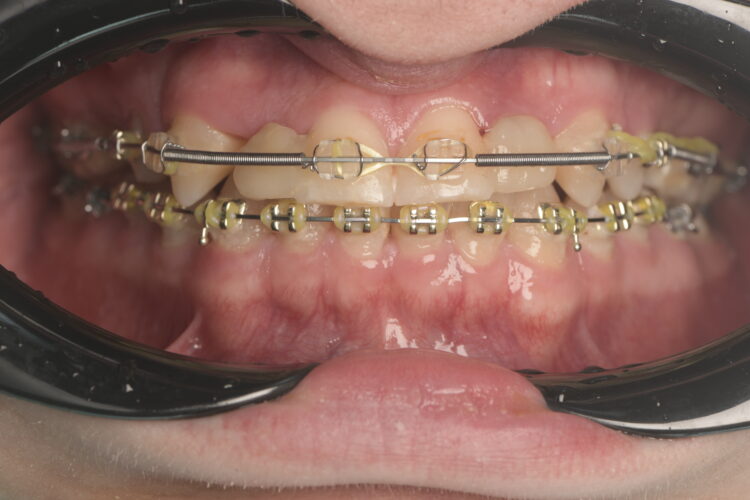

Orthodontic preparation

The orthodontist moved the patient’s teeth into an ideal position, ensuring proper alignment and sufficient space for the implants in the lateral incisor regions. This process took five years, due to the COVID-19 pandemic and the patient’s work commitments, during which time the braces were reviewed and adjusted as necessary.